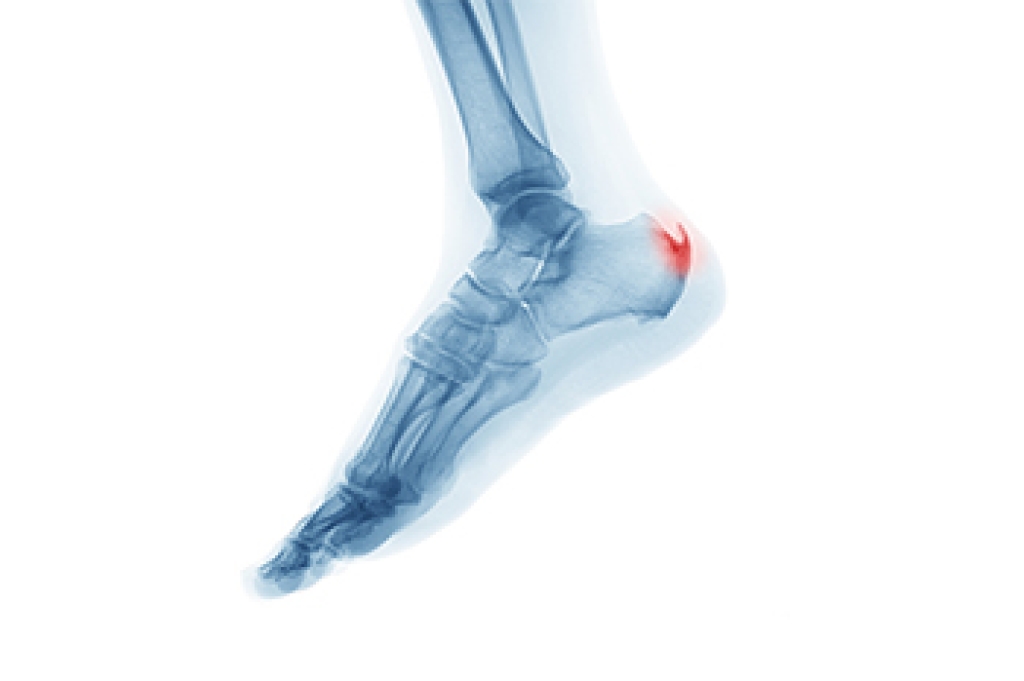

An ankle sprain occurs when the ligaments that support the ankle are stretched or torn. This type of sprain is a common injury, constituting 25 percent of all sports-related injuries. Ankle sprains can affect anyone, not just those engaged in sports. While they are often caused by activities such as running and walking, they also can be the result of missteps on uneven surfaces, such as stepping into a hole or missing a curb. Symptoms vary in severity, and include pain, soreness, swelling, difficulty bearing weight or walking, and bruising. Diagnosis involves a comprehensive examination by a podiatrist, who can evaluate bones, soft tissues, range of motion, and strength. In some cases, imaging studies like X-rays may be ordered to rule out additional injuries, such as a fracture. Timely and proper treatment typically takes between four and six weeks, depending on severity. Acknowledging the causes and symptoms of ankle sprains is important for prompt intervention, ensuring optimal recovery and minimizing the risk of future complications arising from these common injuries. If you have endured an ankle sprain, it is suggested that you schedule an immediate appointment with a podiatrist for an exam and treatment.